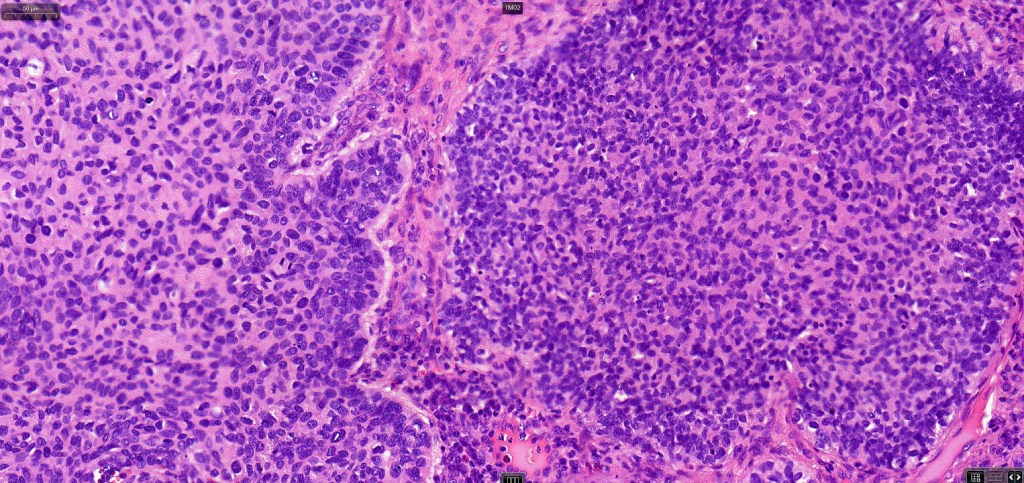

•The epithelial component is composed of uniform small, basophilic devoid of desmosomes

•Peripheral palisading

•Mitoses often very marked

•Apoptosis

. Perineural infiltration & lymphovascular invasion sometimes present

•A wide variety of histological variants are possible including nodular, nodulocystic, ulcerative, superficial, micronodular, infiltrating/infiltrative, keratotic, basosquamous, pigmented, morpheaform, keloidal, clear-cell, signet-ring cell & granular cell variants, BCC with monster cells, BCC with metaplastic features, BCC with matricial differentiation, basomelanocytic tumor (see separate blog), BCC with thickened basement membrane, BCC with carcinoid-like nuclear palisading & these are illustrated below